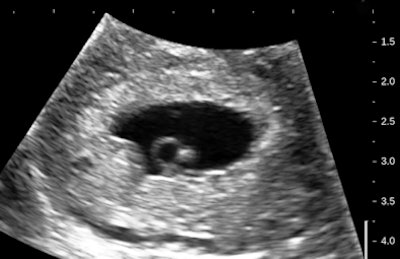

Let's have a look at some selected images from a recent study of a 30-year-old woman with uncertain dates and a positive pregnancy test:

![]() |

There is a intrauterine pregnancy with a (right) corpus luteum with an intact vascular margin. A regular heart rate of 122 beats per minute implies a 6.0-week stage. The Doppler pattern has separate filling and ejection phases. The decidual boundary is thick and well implanted. But there was another unexpected finding when looking at the left ovary: